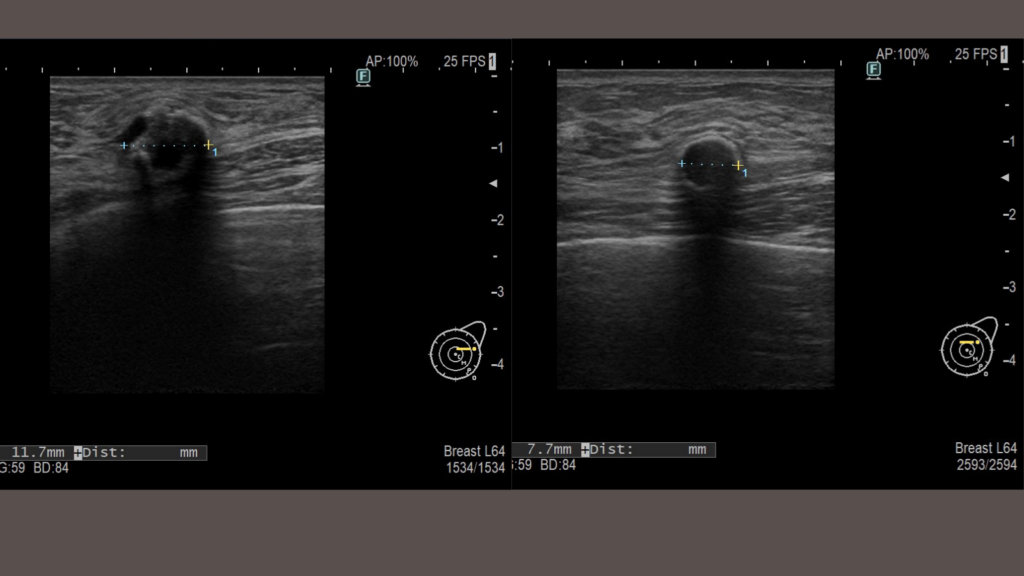

左胸の側胸部側のしこりが気になっていたようですが、エコーでみると、乳輪の頭側にも乳腺下にしこりがあることがわかりました。下縁に創部を設け、丁寧に剥離を進めながら摘出しています。後日、コンデンスリッチ脂肪豊胸も行いました。脂肪豊胸はどんなに気をつけていても、一定の確率でしこりを生じうる施術です。エコーでの診察を整備しているクリニックで必ず行うようにしてください。